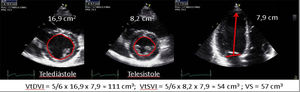

| B.1. Simpson biplanar. El cálculo de la FE por ecocardiografía 2D es el método más aplicado en la práctica clínica en la valoración de la función ventricular. La gran resolución espacial supera las limitaciones de la técnica modo-M, la mejora de los equipos, la adquisición del segundo armónico y los ecopotenciadores permiten una adecuada definición endocárdica en la mayoría de los pacientes. A pesar de que es la técnica más extendida, en ocasiones, especialmente en el postoperatorio de cirugía cardiaca, puede entrañar una complejidad técnica adicional derivada de la dificultad para obtener un plano correcto o identificar adecuadamente el borde endocárdico. Además, su cuantificación, como en otros parámetros, se ve afectada por la situación de la precarga y la poscarga. | ||

| B.2. Método área-longitud. Aplicable en ventrículos simétricos. Método alternativo para calcular los volúmenes del ventrículo izquierdo en los casos con mala definición del endocardio en los cortes apicales (sobre todo a nivel lateral). Los volúmenes son más representativos de las auténticas dimensiones de la cavidad ventricular, y, además, se adapta mejor a los ventrículos con morfología anormal. | ||